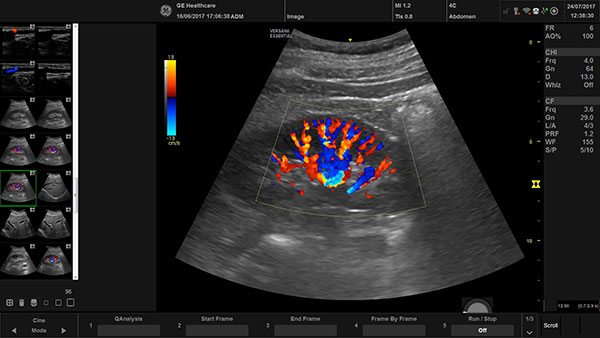

Ultrasonography(USG)

It is a medical imaging technique that uses high-frequency sound waves to create real-time images of internal organs, tissues, and blood vessels. A transducer sends sound waves into the body, which reflect off internal structures and return as echoes.

High Resolution(USG)

It is an advanced imaging technique that uses high-frequency sound waves to create detailed, non-invasive images of superficial soft tissues. It is particularly useful for evaluating peripheral nerves, skin lesions, and other superficial structures, and is used to diagnose conditions like peripheral neuropathies, skin cancers, and nerve injuries from trauma or surgery